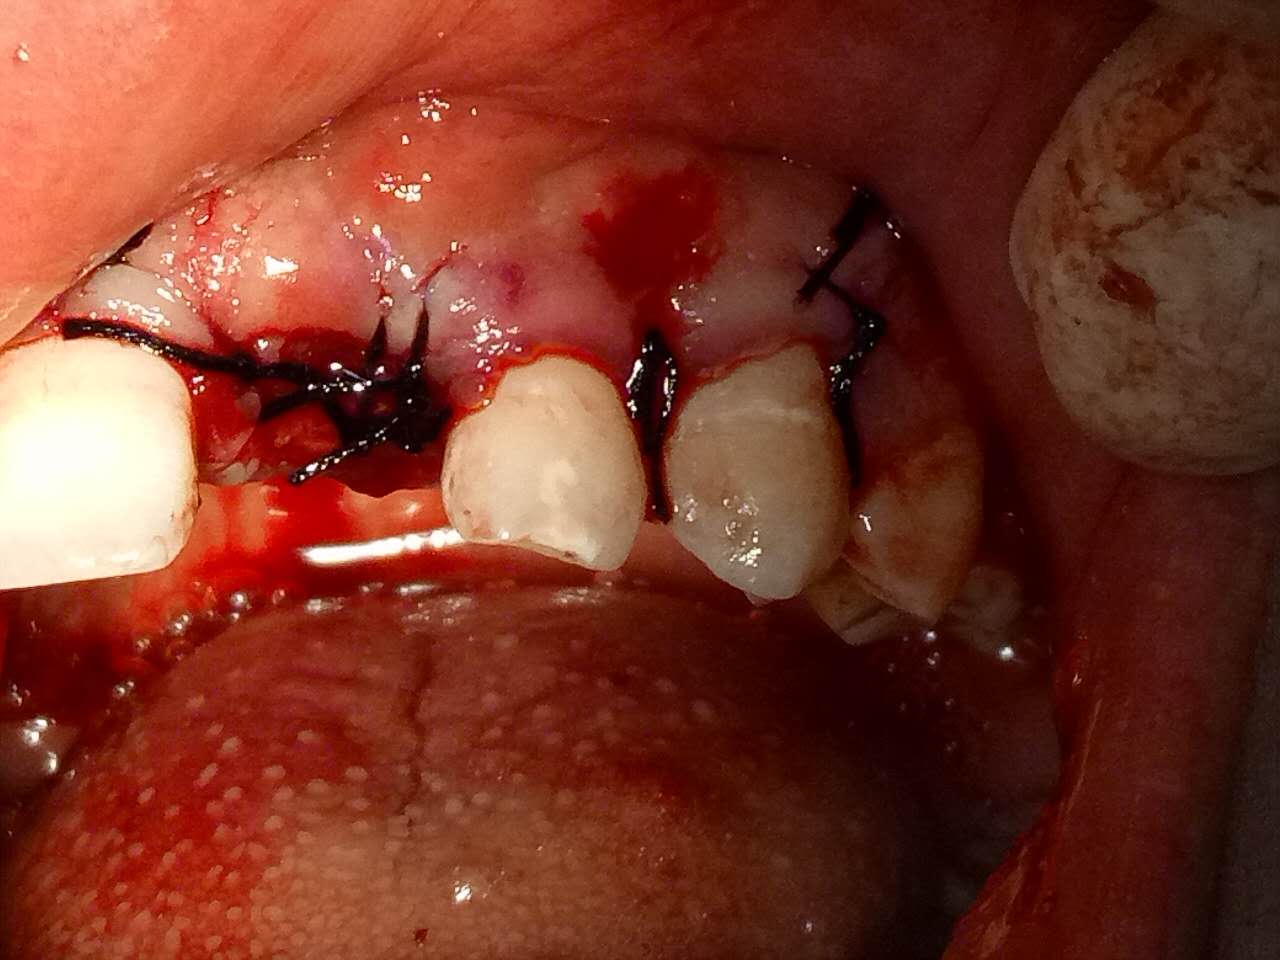

死髓牙2度,沒保留價(jià)值了,外傷造成的外吸收,即使到充也容易出問題。和患者溝通,要求做種植,用了兩個(gè)骨膠原,側(cè)切、尖牙沒事,側(cè)切做了一次根充